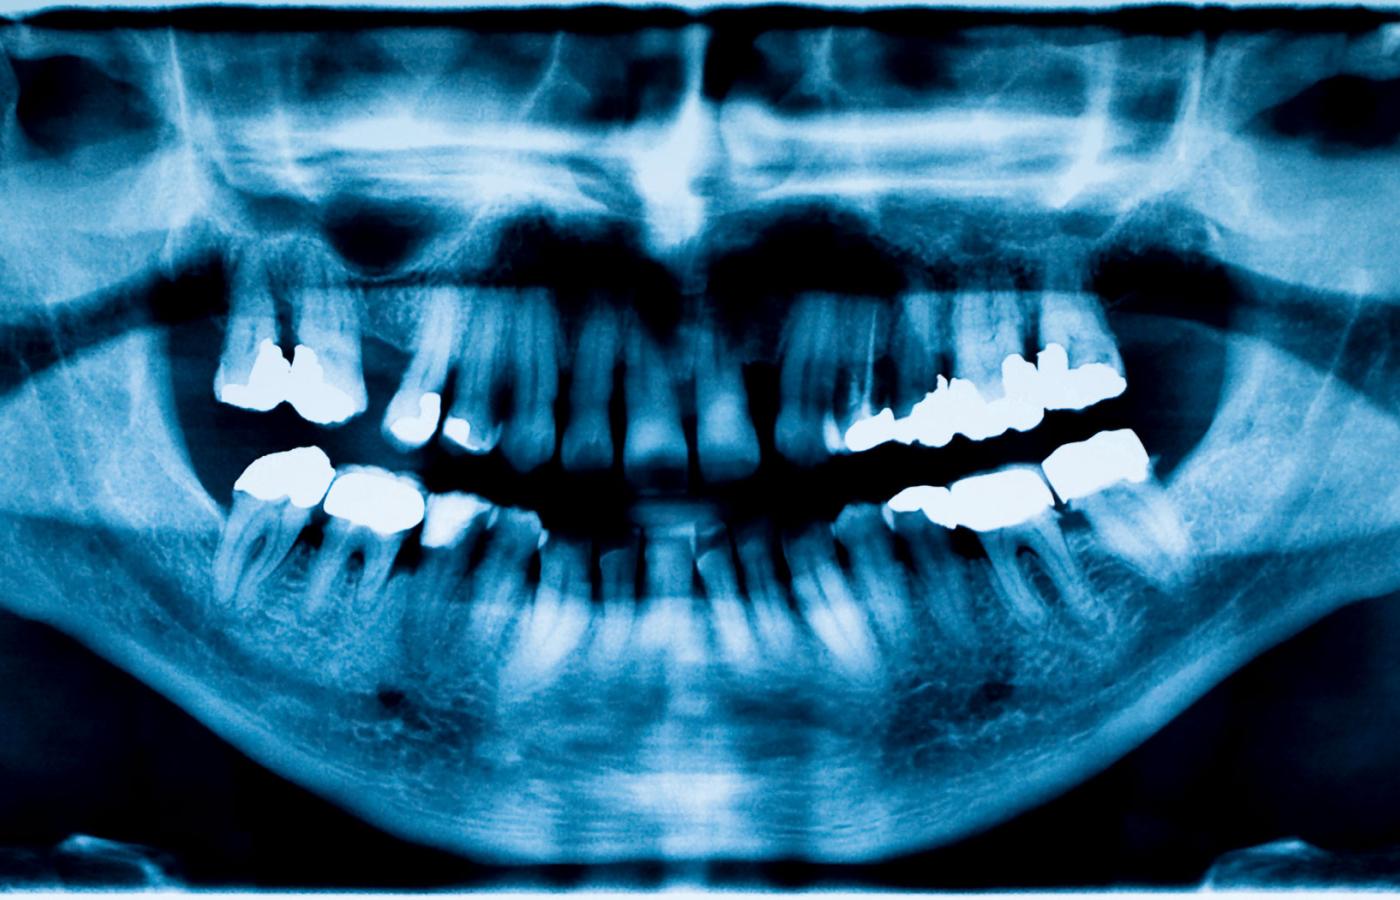

O higienę jamy ustnej trzeba dbać nie tylko ze względów estetycznych. Zadziwiające, jak bardzo uzależniony od niej jest stan naszego organizmu.

Do jednej rzeczy nie można nas przekonać: do właściwej higieny jamy ustnej. Pod tym względem sytuacja jest niemal identyczna jak w czasie, gdy żegnaliśmy się z socjalizmem 26 lat temu. Powtarzane co pewien czas badania sondażowe nie zmieniają się od lat: 3,8 mln Polaków nie myje regularnie zębów, 800 tys. nie ma nawet własnej szczoteczki, zużywamy na głowę 3,5 tubki pasty rocznie, a co 20. obywatel nie korzysta z niej wcale.

Tu nie chodzi już tylko o przeciwdziałanie samej próchnicy, ale o zdrowie całego organizmu – mówi prof.